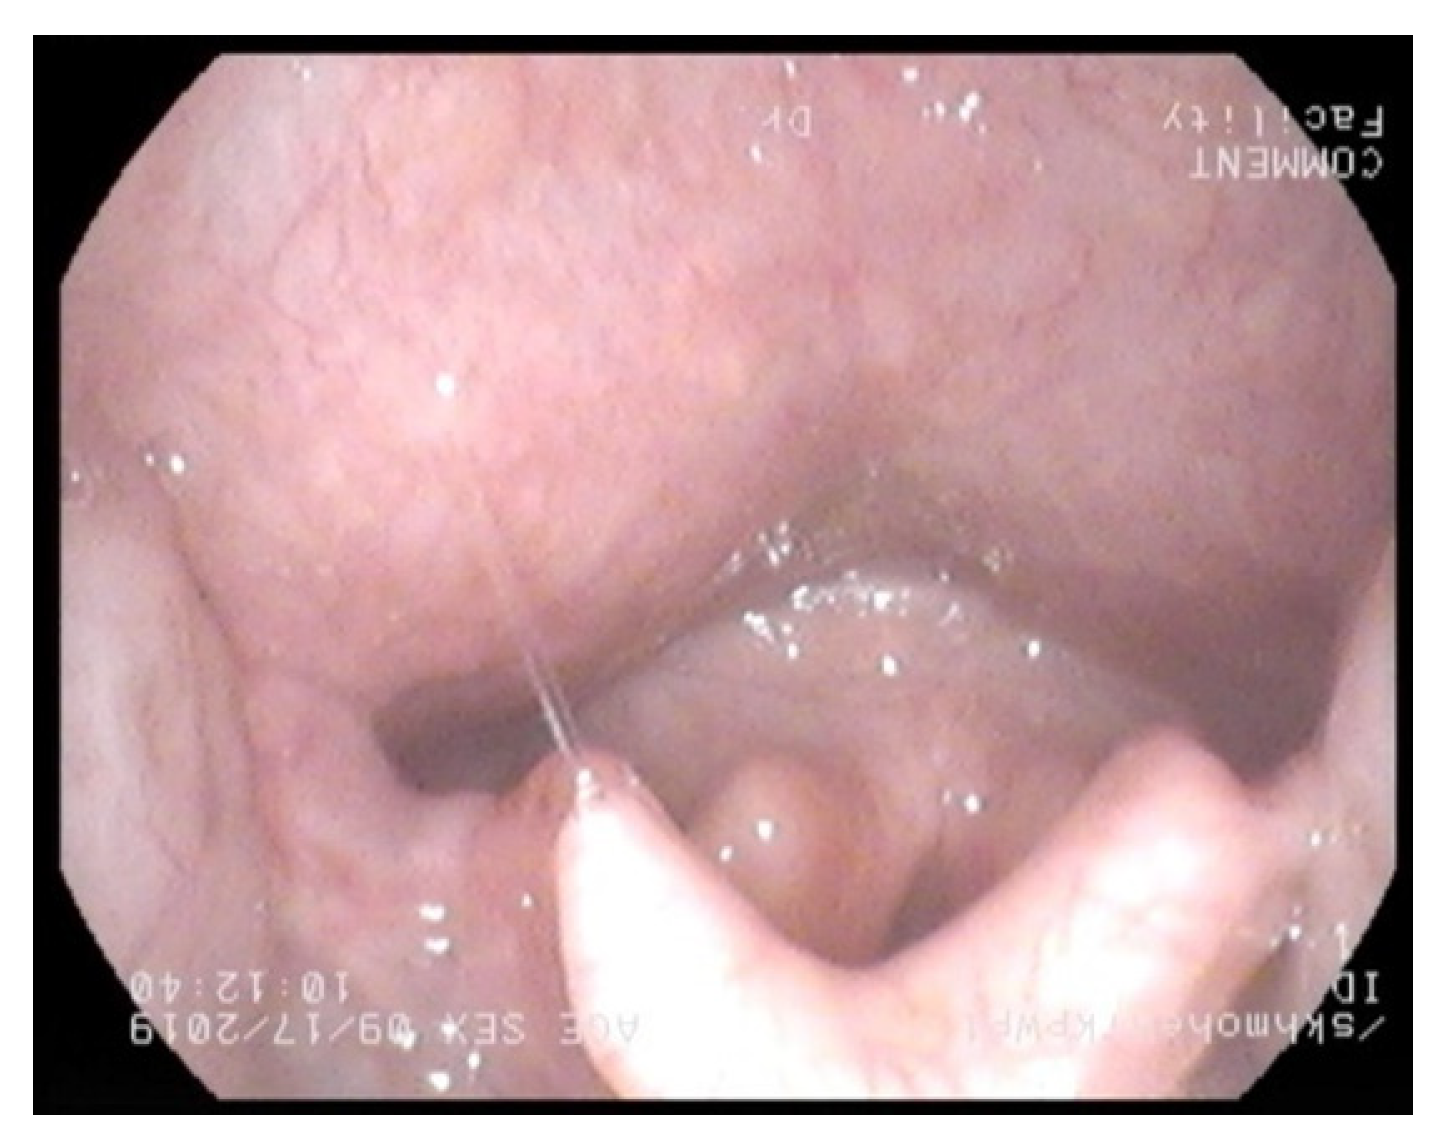

3.1. Nasendoscopy

- Epiglottis bulkiness on nasendoscopy / scan.

- Normal= 0 score (filling less than less than 1/3 of oropharynx)

- Mild bulkiness = 1 (filling 1/3–1/2 of oropharynx)

- Moderate bulkiness = 2 (filling 1/2 to complete oropharynx)

- Severe bulkiness = 3 (filling the entire oropharynx) *

- Supraglottis bulkiness on nasendoscopy/scan.

- Normal= 0 score (filling less than less than 1/3 of supraglottis)

- Mild bulkiness = 1 (filling 1/3–1/2 of supraglottis)

- Moderate bulkiness = 2 (filling 1/2 to complete supraglottis)

- Severe bulkiness = 3 (filling the entire supraglottis) *

- Glottis bulkiness on nasendoscopy.

- Normal = 0 score (filling less than less than 1/3 of glottis)

- Mild bulkiness = 1 (filling 1/3–1/2 of glottis)

- Moderate bulkiness = 2 (filling 1/2 to complete glottis)

- Severe bulkiness = 3 (filling the entire glottis) *